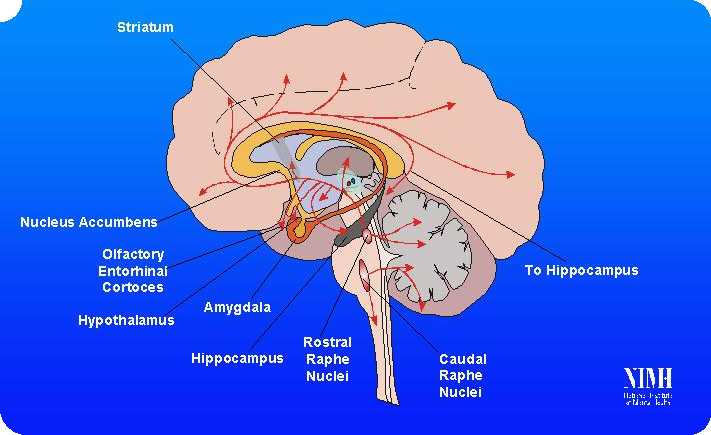

Zum Einstieg in unser Thema zeigt uns die folgende Grafik unser Serotoninsystem und seine Nervenbahnen im Gehirn:

Unser Serotoninsystem